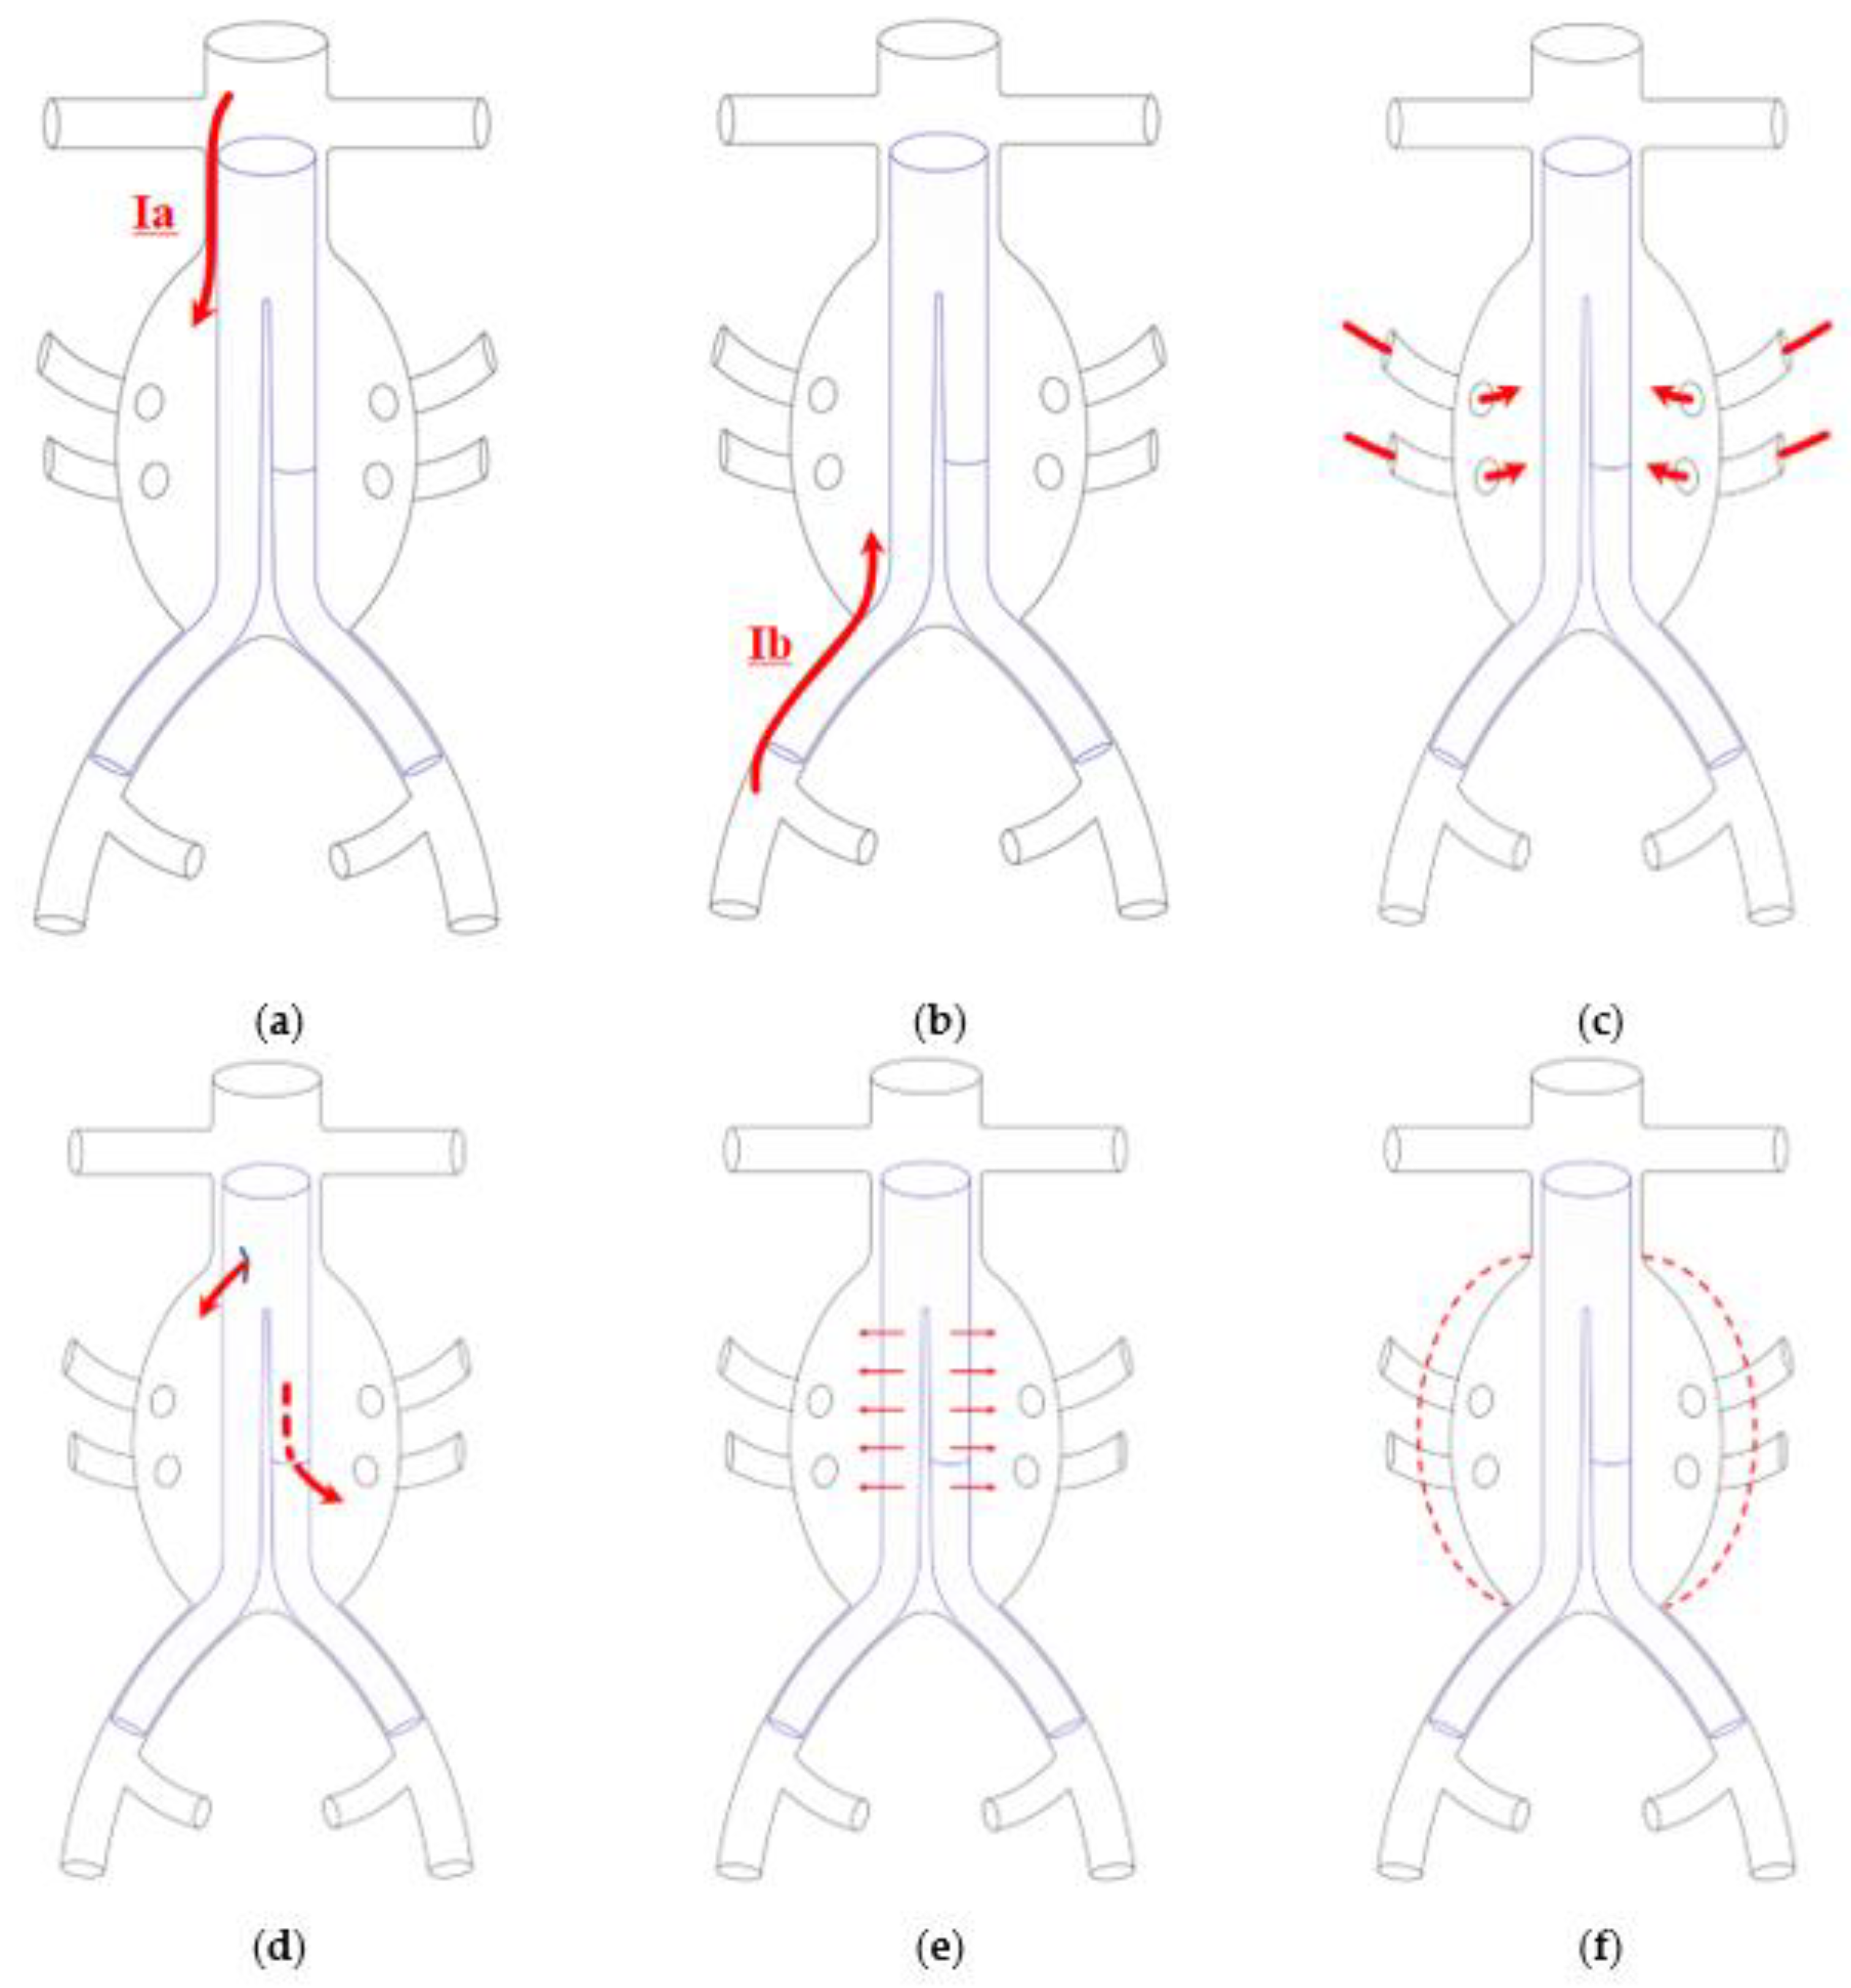

1. Introduction

4. Discussion